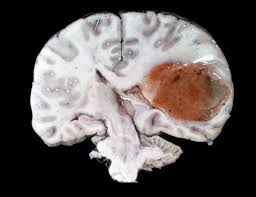

Brain Cancer Causes Types Symptoms Treatment Stages Survival Rate from images.medicinenet.com People exposed to very high doses of radiation to the head. There is no definitive cause of brain tumors or brain cancer, though certain factors may increase the risk. In the past two decades brain tumor rates have risen in several industrialized countries, including the united states. As the tumor grows, it creates pressure on and changes the function of surrounding brain tissue, which causes signs and symptoms such as headaches, nausea and balance problems. The incidence increased by 35 percent in children younger than 15, according to the website pediatric oncology education materials, which provides information for healthcare professionals. A brain tumor is a mass or growth of abnormal cells in your brain. A brain tumor can form in the brain cells (as shown), or it can begin elsewhere and spread to the brain. Some brain and spinal cord tumours are more common in people with certain inherited or genetic conditions.

There is no definitive cause of brain tumors or brain cancer, though certain factors may increase the risk. Glioblastomas (the type of brain cancer linked to cell phone radiation) and central nervous system tumors are increasing in young americans, in precisely the areas of the brain that absorb most of the microwave radiation emitted or received by phones. An estimated 4,630 new cases of pediatric brain tumors will be diagnosed in the u.s. A primary malignant brain tumor is a rare type of cancer accounting for only about 1.4% of all new cancer cases in the u.s.the most common brain tumors are known as secondary tumors, meaning they have metastasized, or spread, to the brain from other parts of the body such as the lungs, breasts, colon or prostate. This can be caused by growth of the tumor itself, swelling in. However, some specific types of brain tumors, such as meningioma, are more common in women. These brain tumors are usually benign. A brain tumor, known as an intracranial tumor, is an abnormal mass of tissue in which cells grow and multiply uncontrollably, seemingly unchecked by the mechanisms that control normal cells. Bigger brains have more brain cells, and thus a greater potential for cell mutations that lead to cancer. A brain tumor can form in the brain cells (as shown), or it can begin elsewhere and spread to the brain. Cancers that begin in the brain do not appear to be increasing. In general, men are more likely than women to develop a brain tumor. Recently, an increasing incidence of brain tumors has been reported from multiple studies.

However, some specific types of brain tumors, such as meningioma, are more common in women. In the past two decades brain tumor rates have risen in several industrialized countries, including the united states. The incidence rate for a type of brain tumor called glioblastoma more than doubled in england between 1995 and 2015, a study finds. This year, an estimated 24,530 adults (13,840 men and 10,690 women) in the united states will be diagnosed with primary cancerous tumors of the brain and spinal cord. A primary brain or spinal cord tumor is a tumor that starts in the brain or spinal cord.